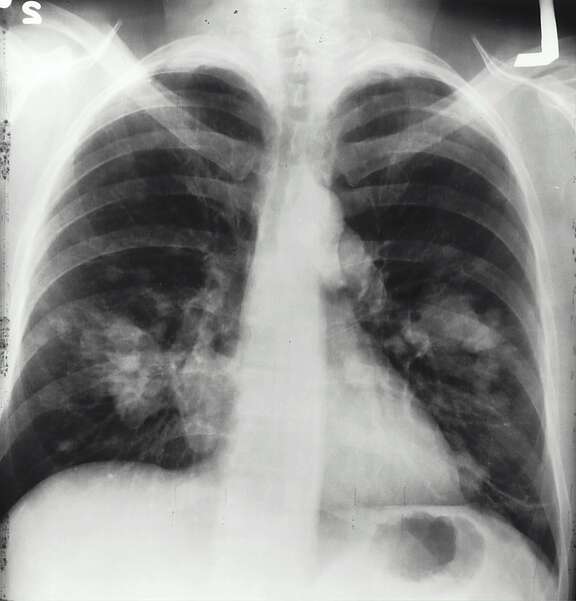

- Malattie legate al fumo